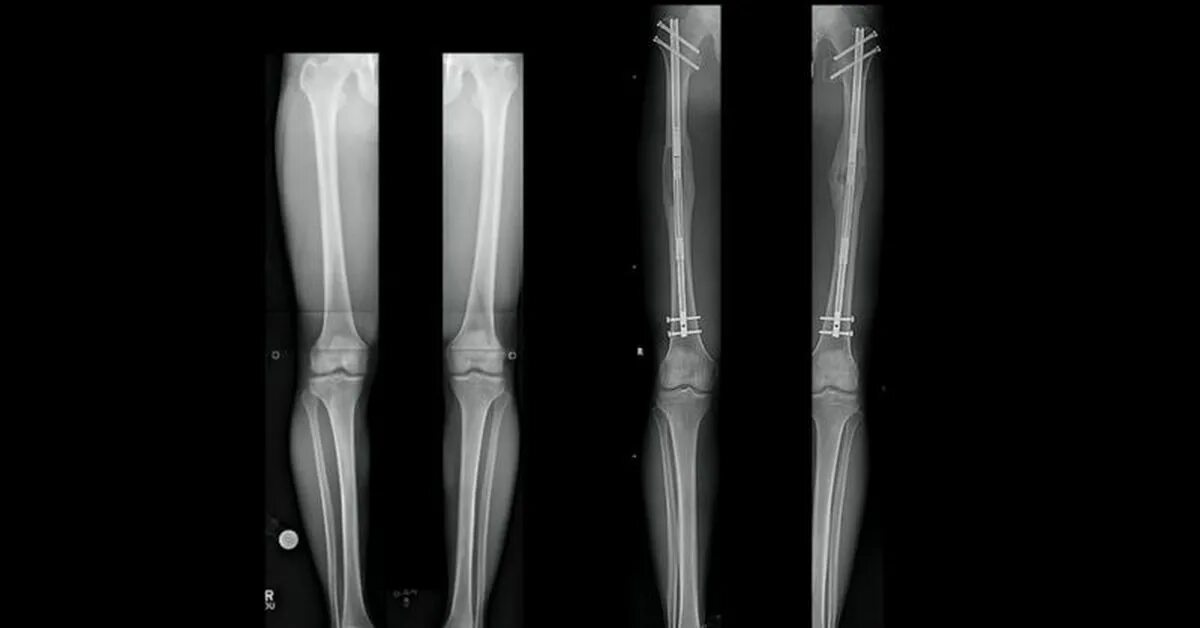

Увеличение роста операция см